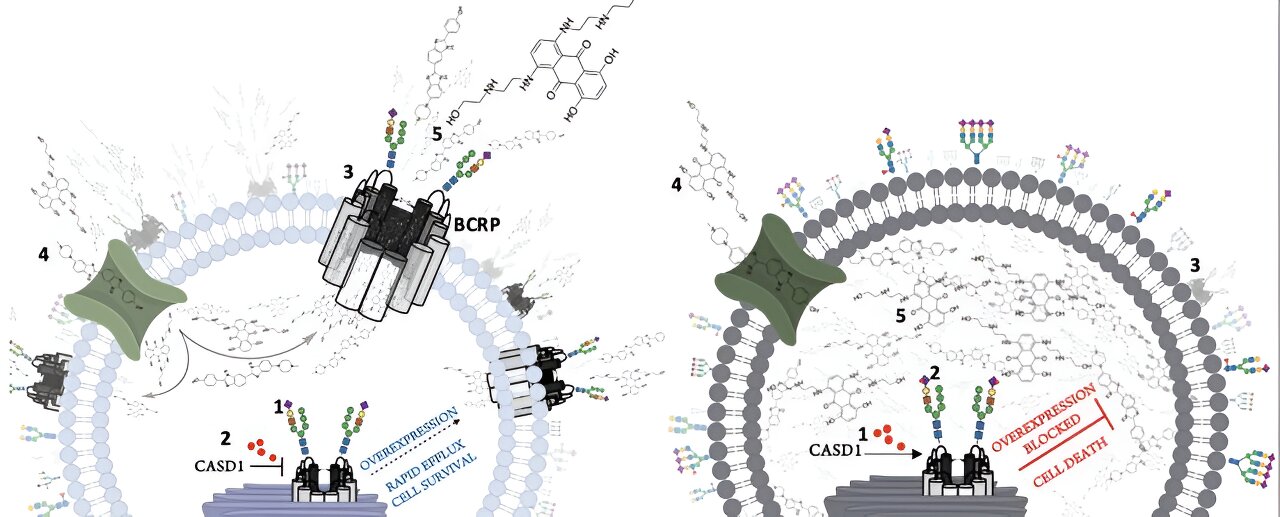

Study reveals insights into how cancer cells evade treatment